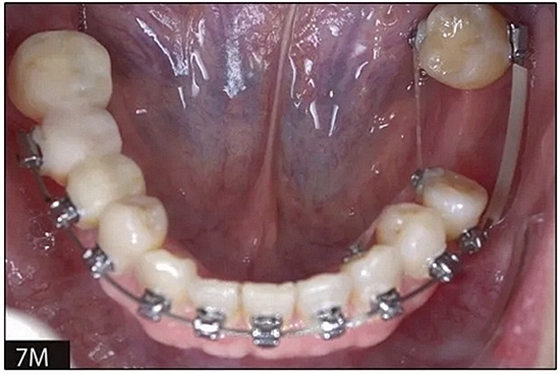

完全固定的Damon Q設備(加利福尼亞州Glendora的Ormco)與制造商指定的弓絲和附件一起使用。下頜弓,一開始放入0.014英寸的鎳鈦弓絲,5個月后放入0.014×0.025英寸的鎳鈦弓絲。舌側扣和鏈圈放置在下頜尖牙和第二前磨牙上以控制扭轉。在治療的第7個月,將下頜弓絲換成0.017× 0.025英寸的β鈦絲。另一個舌側扣和鏈圈放置在下頜左側第三磨牙上以提供近中牽引力(圖9)。在16個月的治療結束時,所有的扭轉都得到了矯正,缺牙間隙縮小到8 mm(圖8),但由于頰側骨板的嚴重吸收,牙槽嵴的寬度仍然很窄(約3 mm)(圖9)。通過正畸移動下頜左側第二前磨牙,在前磨牙之間產(chǎn)生一個種植部位。在第一和第二前磨牙之間的弓絲上放置一個推簧,并將舌側扣和鏈圈放置在第一前磨牙和第三磨牙之間(圖9),在頰側和舌側施加力。施力均為輕力,每個表面上約2盎司(28.3 cN)以控制牙根側面的吸收。

圖8

圖9